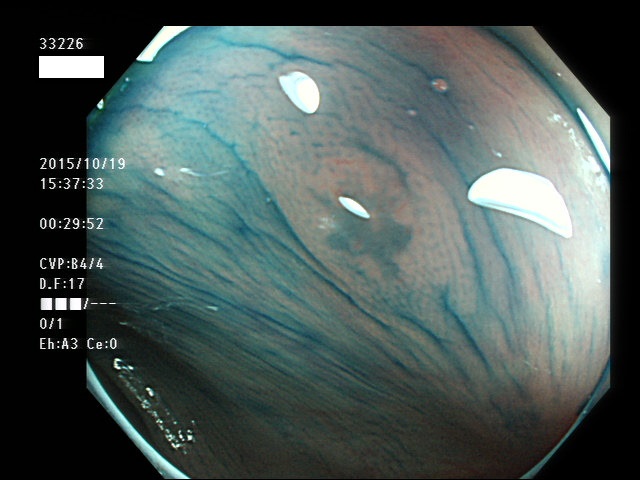

上記100名より抽出した平坦・陥凹型腺腫(=癌化の危険が高いが見落としやすい病変)の内視鏡写真